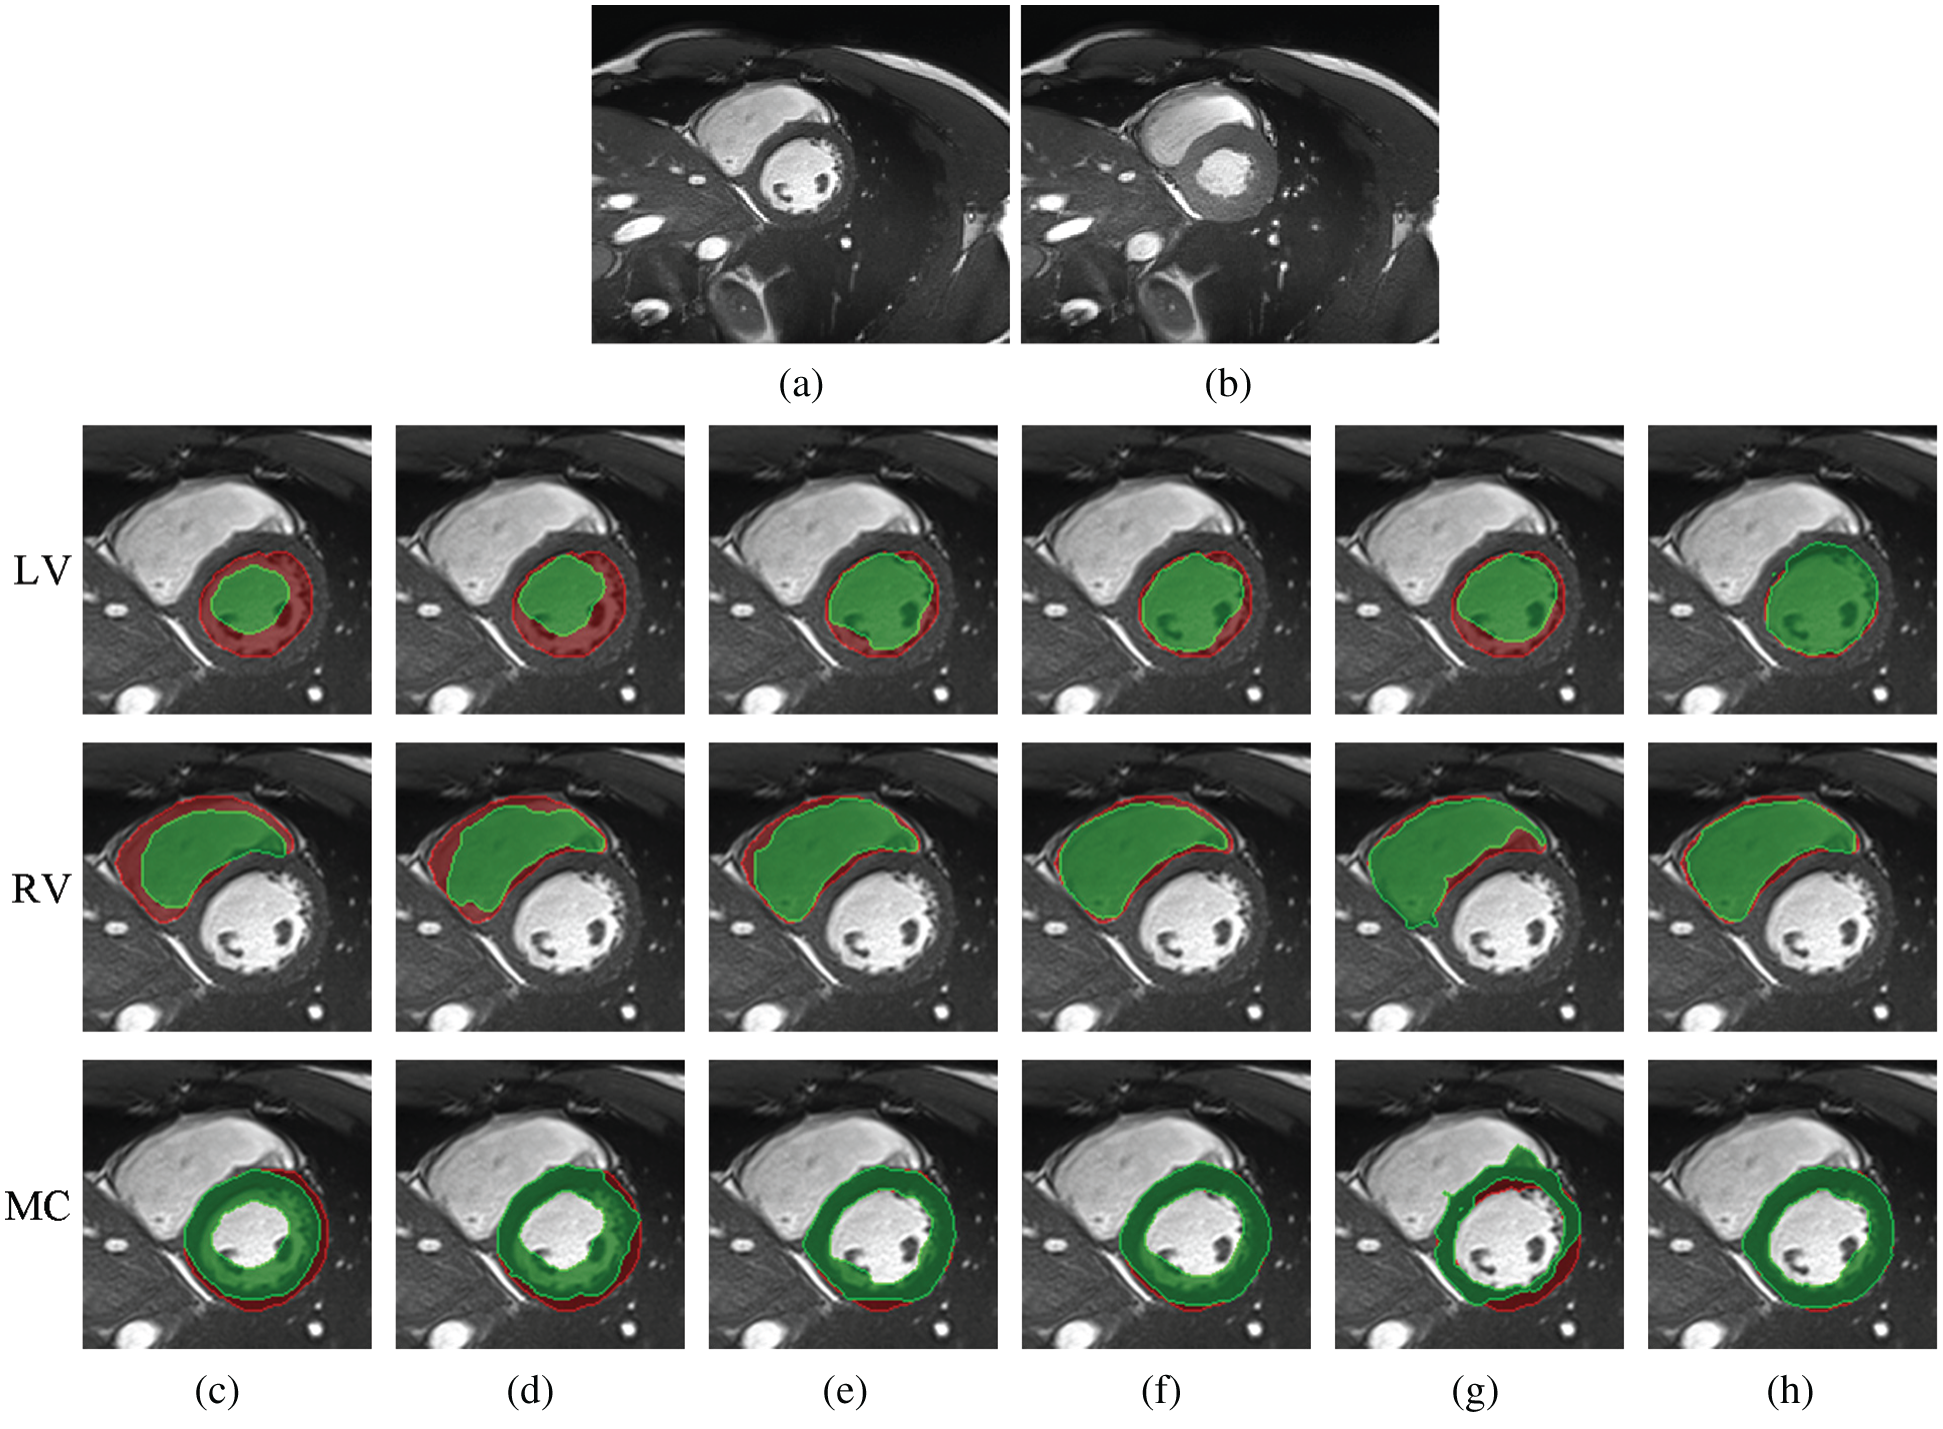

Large deformations due to heartbeat and respiration effects lead to a challenging deformable image registration task. In this section, we investigated registration performance in the case of the large deformable motion of cardiac tissue from ACDC for the five compared methods. The cardiac cine MRI scans in ACDC consist of short-axis cardiac image slices, each containing 20 time points that encompass the entire cardiac cycle. An expert annotated the LV, the RV and the MC at end diastolic (ED) and end systolic (ES) time points. To facilitate quantitative evaluation, we took the images in the ED and ES phases as fixed and moving images, respectively. We also trained the Siamese network on the image patches taken from the MR slices from BrainWeb and EMPIRE10, and the testing images were randomly selected from ACDC (unseen dataset and body part).

Tab. 4 shows the average DICE of the annotated LV, RV and MC regions that correspond to the registered images obtained by the five methods for ED and ES frames from the ACDC dataset. Tab. 4 shows that the proposed Siamese Flow achieves the highest average DICE.

Fig. 9 shows a comparison among different registration algorithms with large deformations and unseen datasets. Fig. 9a shows one fixed image randomly selected from ACDC; Fig. 9b is the corresponding moving image at the ES time point; and Figs. 9c–9h are superimposed LV, RV and MC regions of the ground truth (red) and the deformed regions of the registered image (green). Specifically, Fig. 9c is the result before registration; and Figs. 9d–9h are the results after registration using Demons, SIFT Flow, Elastix, VoxelMorph and Siamese Flow, respectively. Fig. 9 shows that the deformed region attained by Siamese Flow achieves the closest alignment with the ground truth region.

Figure 9: Example results for large-deformation cardiac-motion registration. (a) Fixed image (ED time point) (b) Moving image (ES time point) (c) unregistered (d) Demons (e) SIFT Flow (f) Elastix (g) VoxelMorph (h) Siamese Flow

Better registration is reflected by closer alignment of the fixed and moving images. Based on the DICE results in Tab. 4 and the superimposed LV, RV and MC regions in Fig. 9, Siamese Flow is shown to be capable of managing large tissue or organ deformations and achieves the best performance among all investigated methods. The Demons approach fails to align two images because the underlying assumptions (constant gray values and constant gradient) are unsatisfactory in optical flow estimation. VoxelMorph fails to attain accurate registered results due to the large unseen deformation level. SIFT Flow obtains alignment results that are comparable to those of Elastix for this large-deformation registration task. Elastix fails to align two images under a certain iteration number (e.g., 500 iterations). SIFT Flow also fails to use the handcrafted SIFT feature. In contrast, Siamese Flow is successful in all of these cases because the learned image patch representation is robust and generalizable, even to large deformations.

Furthermore, Tab. 4 and Fig. 9 show that Siamese Flow can generalize different tasks without retraining the model. The model learns a generic local descriptor that is applicable to other unseen datasets (ACDC) and unseen body parts (cardiac).